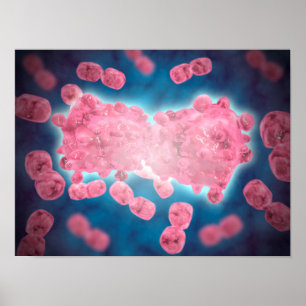

Poster Image Conceptuelle De Mitochondria 3

Prix30,15 $CA